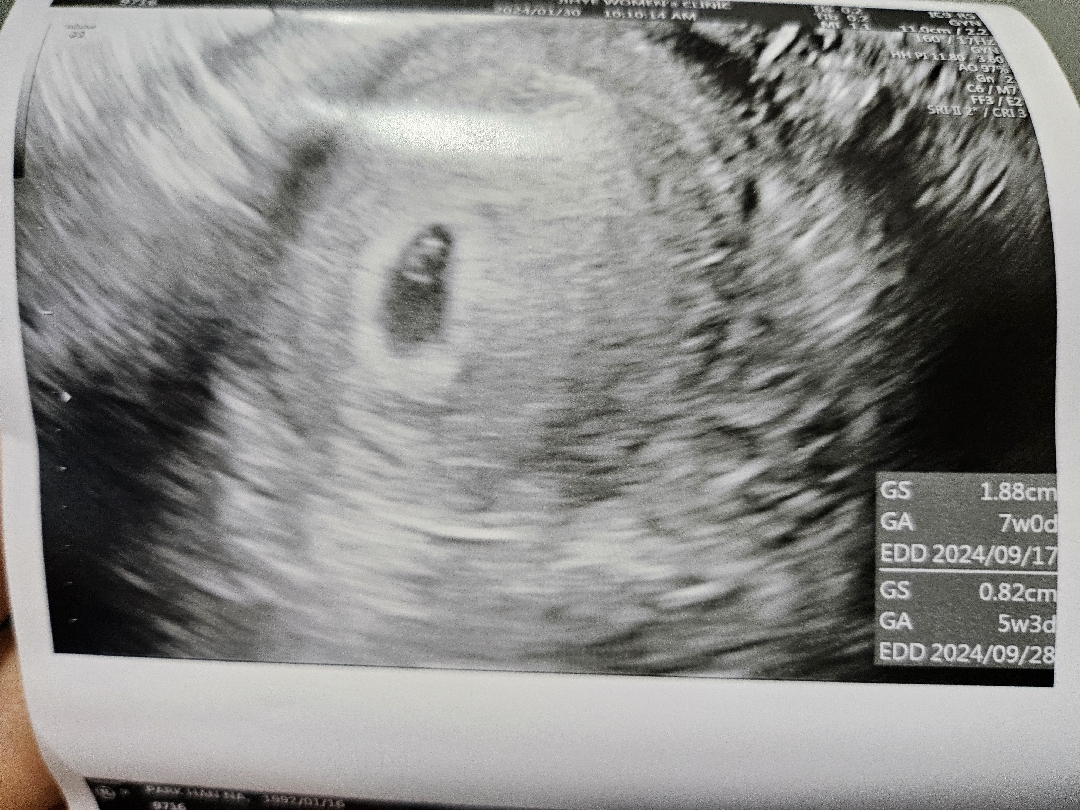

1월30일에 아기집보구 저기잇는게 난황같다하셨는데 2월7일에가면 아기랑 심소들을수있을까요? 설에 임밍아웃하려는데 아직아기를못봐서 찝찝해서요ㅠㅠㅠ

2월 7일이면 6주정도되니 난황이랑 심소 들을 수 있으실거예요!😊 설에 임밍아웃 꼭 하실 수 있을 거 같으세요